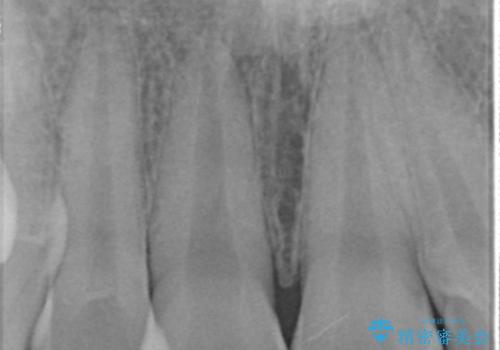

- 前歯の変色を主訴に来院。

神経が死んでいたため、神経の治療を行いました。

神経が死んでしまった歯は時間がたつと変色してきてしまいます、セラミックでかぶせると色を改善することが可能です。